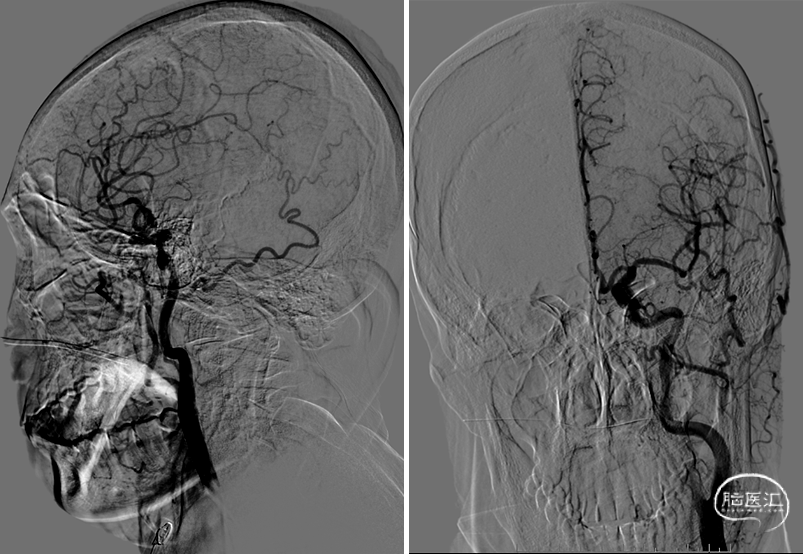

300cm微导丝携Gateway球囊到位,行球囊扩张及预扩张后造影。

1、本例患者反复出现神经功能障碍,血管评估提示双侧椎动脉V4段均为重度狭窄,左侧狭窄位置位于发出小脑后下动脉下方,紧邻小脑后下动脉,同时左侧小脑后下动脉起始段存在有重度狭窄,相对粗大。

2、右侧椎动脉V4段血管狭窄附近未见有明确血管分支,因此手术选择了行右侧椎动脉V4段球囊扩张及支架置入术,因双侧椎动脉V4段狭窄以远椎动脉及基底动脉汇合处血管良好,因此右侧椎动脉V4段狭窄处支架置入术后病人右侧椎动脉及远端基底动脉血流明显改善外,同时也可见到左侧椎动脉V4段逆向显影至左侧小脑后下动脉。同时避免了左侧椎动脉支架置入术中对左侧小脑后下动脉的影响导致小脑后下动脉缺血事件发生的可能。

3、Gateway球囊为半顺应性球囊,推送性能良好,术中缓慢扩张,可减少球囊移位、血管变形及夹层等,为后续支架置入提供了良好的条件。

4、EZ支架通过性好,释放顺畅,径向支撑力强,支架贴壁良好。